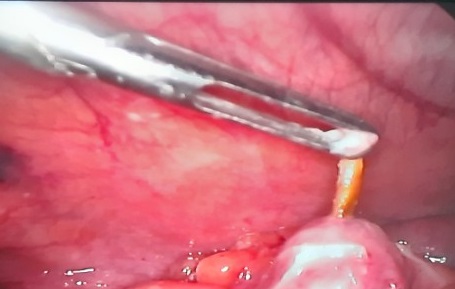

Một trường hợp thủng ruột do xương gia cầm được phẫu thuật

tại BVĐK Quảng Trị